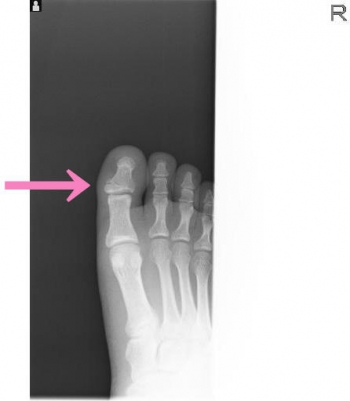

今日、ご紹介するのは、足・足指 足指骨骨折についてご紹介していきます。

足指骨は、四肢動物の後肢の先端部にある、足の指を構成する骨の集合です。

基節骨・中節骨・末節骨で構成される骨の集合で、動物の手足において、指に相当する部分を構成している。

手足の中心部分を構成する中手骨・中足骨とは基節骨が接し、中節骨、末節骨の順に繋がっています。

足指骨骨折

足指骨骨折の発生機序

直達外力では、重量物の落下が多い

介達外力では足尖から衝撃が加わり発生。

基節骨骨折、とくに第1、2指は足底凸の変形が残り、荷重および歩行障害が起こりやすいです。